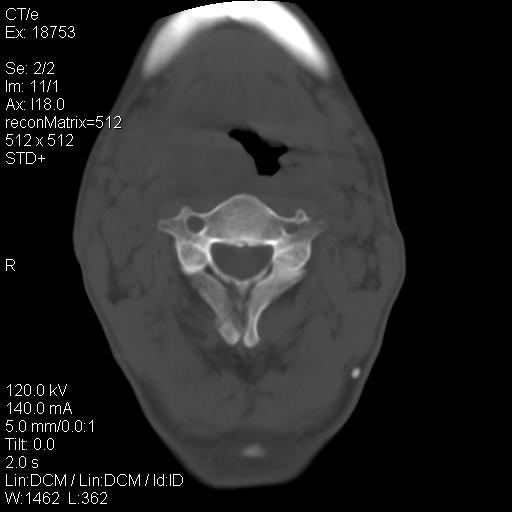

标题: CT21693:男 58岁 右侧咽部疼她2天余 PE:右侧扁桃体肿大 压痛 [打印本页]

标题: CT21693:男 58岁 右侧咽部疼她2天余 PE:右侧扁桃体肿大 压痛

结合病史,考虑感染性病变;建议抗炎治疗复查排除肿瘤性病变。

弥漫性肿胀,与周围组织分界不清,发病急,有明显症状,考虑:感染性病变! 抗炎后复查。

右化脓性扁桃体炎症伴咽后壁脓肿形成.